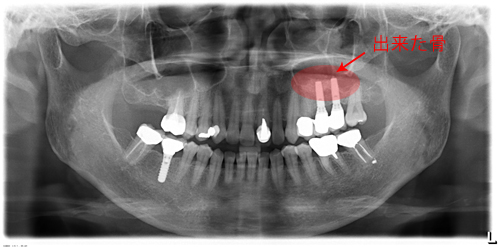

歯周病と根の治療を終わらせた後でインプラントを埋入しました。今では何でも噛めます。

奥歯は骨が少なく、骨をつくり、インプラント治療をしました。赤く囲ったところが出来た骨です。